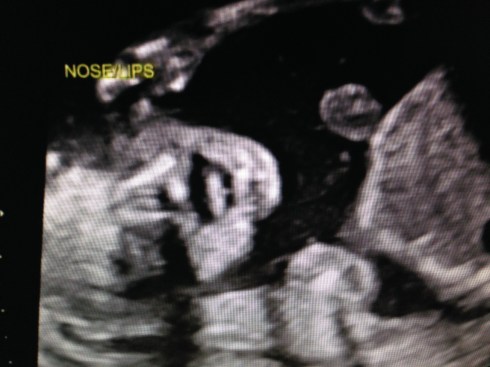

The ultrasound was performed on Friday, March 21, 2014 (at 19 weeks + 4 days). Our boy appeared healthy in all ways and weighed about 10 oz. His growth measurements were between 43% and 62% for his gestational age, and the heart rate was 147 bpm. The placenta is posterior and without previa. My cervix is long. Excellent!

We received a DVD of the scan. I took this short video clip with my phone, that shows baby’s face: moving his jaw, yawning, moving his tongue, and even smiling. You can also see his forearm in front of his face. Watch it again and look for the heart beating. Precious!!

I took these images by pausing the DVD and taking screen shots: